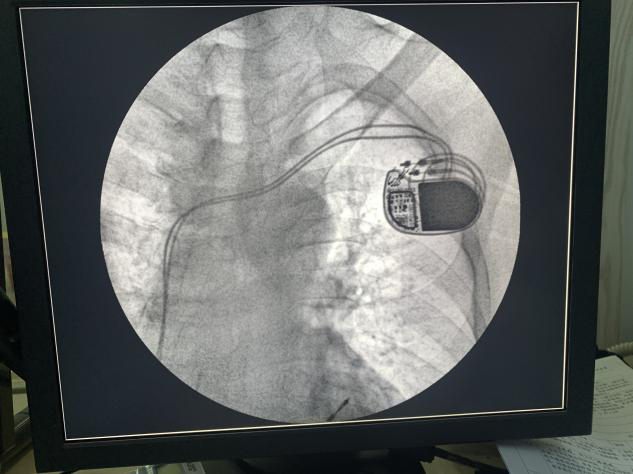

自2021年9月双辽市中心医院心内科成功开展了“心脏双腔永久起搏器植入”的新技术,为各种缓慢性心律失常的患者带来了福音。术后所有患者病症得到显著缓解,生活质量明显提高,得到患者及家属的高度好评。

心脏起搏器是一种植入于体内的电子治疗仪器。心脏的功能主要是收缩舒张,将血液运送到人体的大脑及全身。若患者的窦房结功能异常,可出现心跳过慢的情况;患者的冲动传导路径阻塞,则会造成指示传导错误,也会出现心跳次数减少。心跳过缓会造成大脑及全身供血不足,可导致患者出现晕厥、黑蒙,甚至摔倒、猝死。心脏起搏器则可以发出并传导正确的指示,保证心脏可以按照节律进行收缩舒张。

今年,随着国家惠民政策,心脏起搏器国家集采,大大减轻了患者的经济负担,使患者可以在承担最低费用的同时获得最高质量的医疗服务。2022年2月12日在吉林大学中日联医院闫明洲教授的协助下又成功为一位患者植入一枚双腔永久起搏器,此项技术在双辽市中心医院心内科已经逐渐成熟。